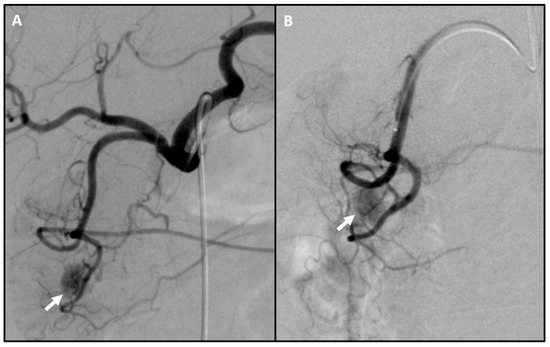

2. Non-Invasive Pre-Operative Localization